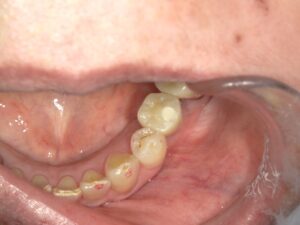

埋入から4ヶ月後、上部構造が入ったところです。